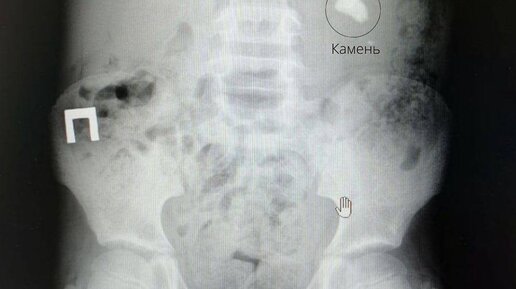

Мочекаменная болезнь находится в топе урологических проблем: с ней сталкивается до 10–15% населения Земли, причем многие — в возрасте 20–50 лет. Камни бывают очень разные по размеру — от подобных песку и размером в 1 мм до рекордных образований более 15 см, занимающих все протоки в почке. Почему могут появиться камни и как избавиться от них — разберем в статье. Мочекаменная болезнь (МКБ, уролитиаз) — состояние, при котором в мочевыделительной системе — почках, мочеточниках, уретре, иногда мочевом пузыре — образуются песок и камни...